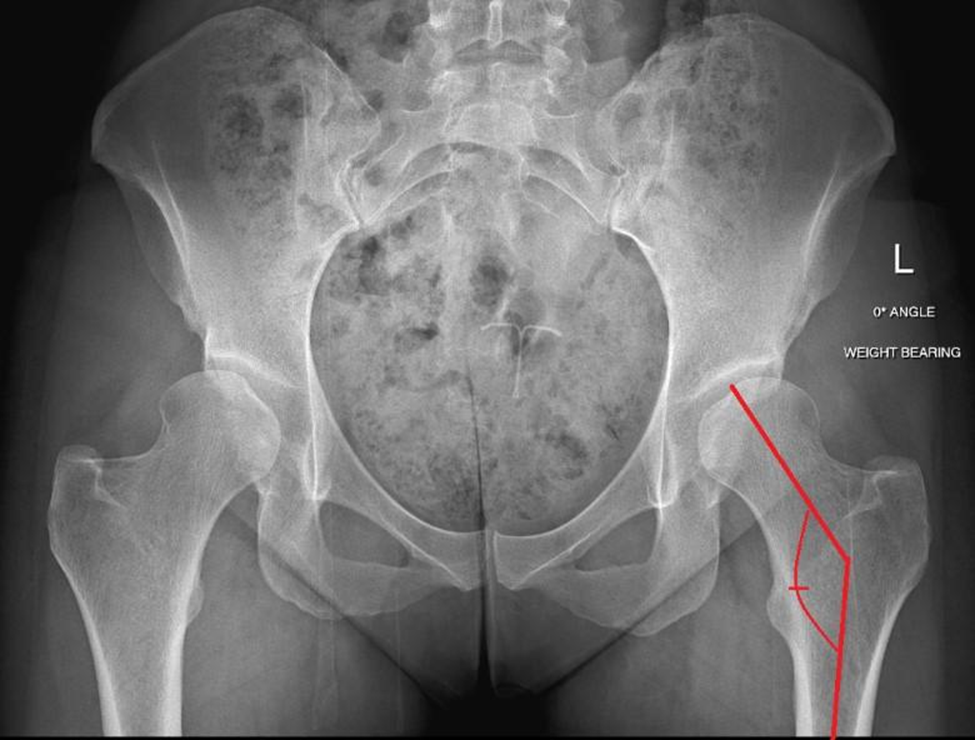

Femoral Neck-Shaft Angle

This angle is formed by the line going from the center of the head of the femur down the middle of the “neck of the femur” (this is the part of the bone that connects the head (ball) of the femur to the long bone of the femur (shaft)). This measurement is used to diagnose hip conditions like hip dysplasia, FAI, Legg-Calve-Perthes disease, avascular necrosis, osteogenesis imperfecta, and fractures up near the top of the femur. This angle may be too high or too low in people with hip problems.

Normal angle =125-135 degrees

< 125 degrees = “coxa vara” (“varus”)

> 135 degrees = “coxa valga” (“valgus”)